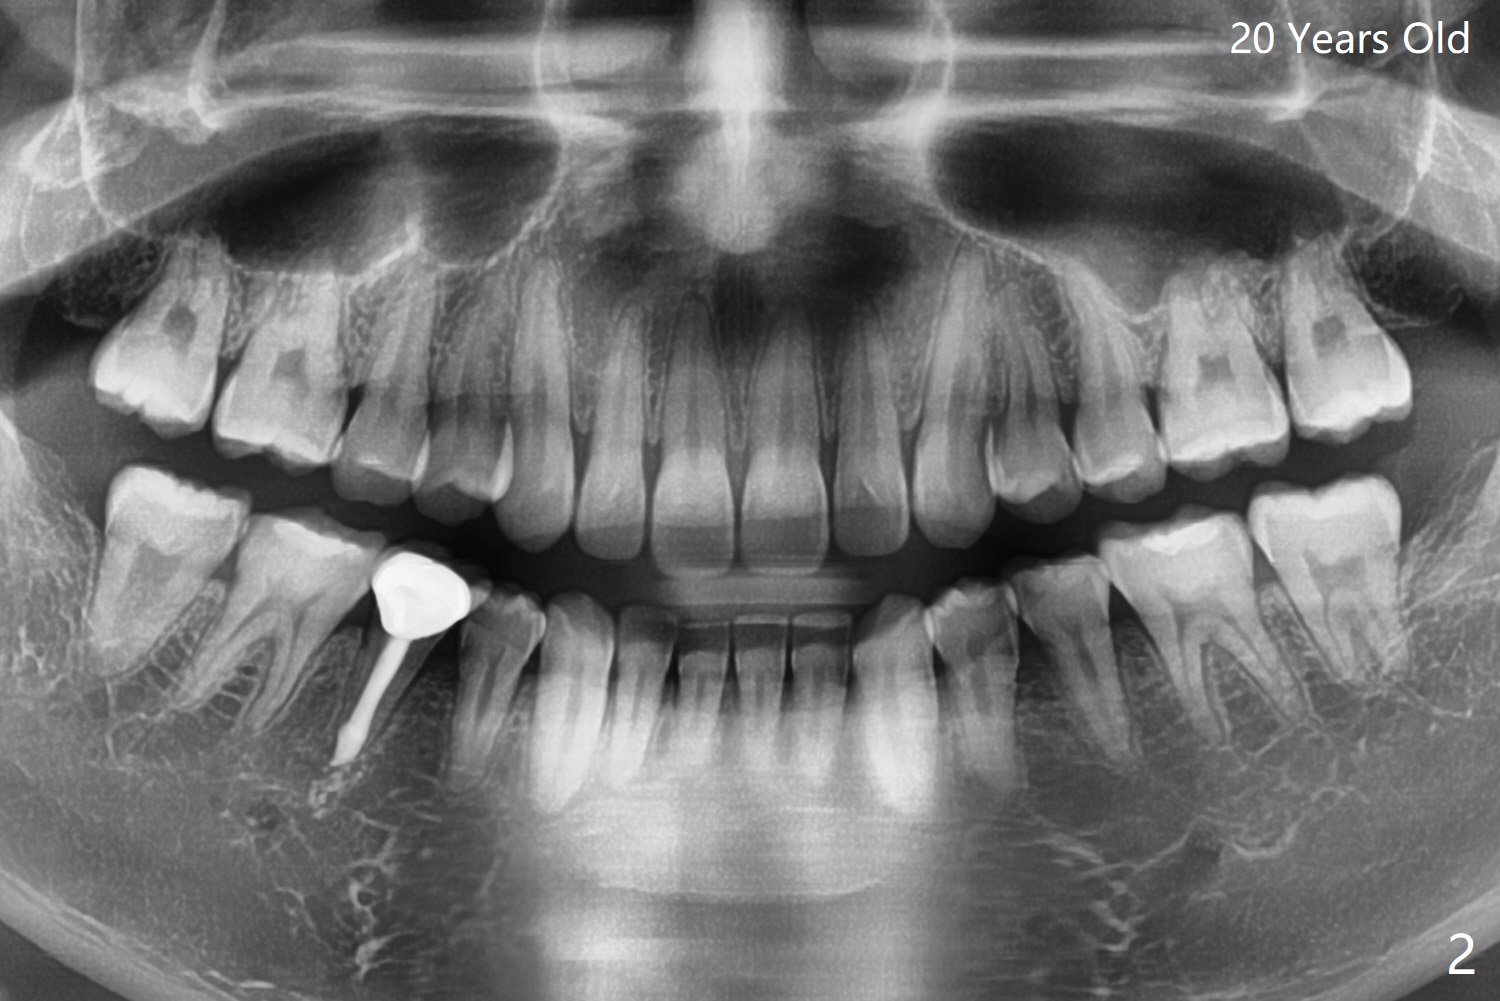

Supernumerary Premolar

A 20-year-old man returns to clinic for periodic exam. A panoramic X-ray film was taken ~ 2 years earlier (Fig.1). What should be done with the supernumerary premolar? With further development of the root of the extra tooth, root resorption of the neighboring teeth may occur. In fact, there is no root resorption of the neighboring teeth post extraction (Fig.2).